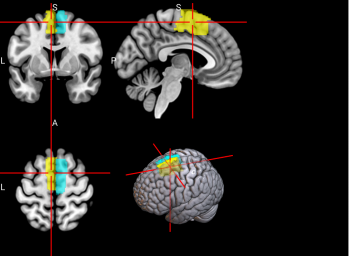

15,

16

L & R Supplementary motor area (SMA)

The SMA plays a role in self-initiated (voluntary) actions and is part of multiple voluntary motor loops [62].

/word/media/image11.png/word/media/image11.png